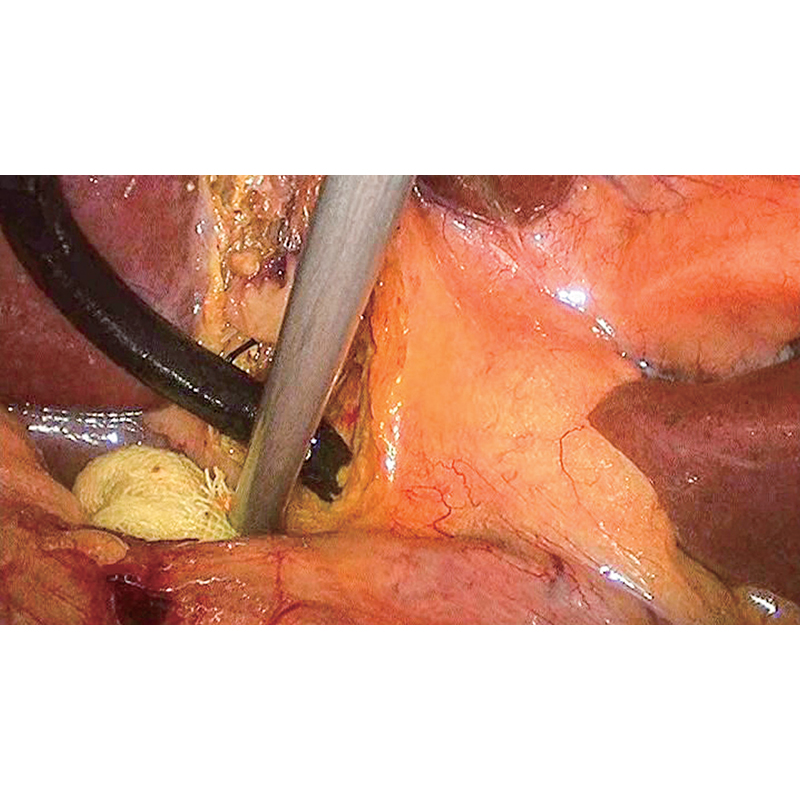

10 mm HD 腹腔鏡 ( 4K UHD 腹腔鏡 とも呼ばれる) は、腹腔鏡手術 における視覚化を再定義するために設計された最先端の内視鏡機器です。向けに調整された 泌尿器科、, 婦人科、および 一般外科この腹腔鏡は、外科医が複雑な手術中に正確な判断を下せるようにする、鮮明で歪みのないイメージングを実現します。外径 10 mm、作動長 320 mm で、アクセスしやすさとパフォーマンスのバランスが取れており、小さな血管、繊細な組織、および低コントラストの構造を明確に視覚化できます。 XISHAN 超高精細内視鏡システムと互換性のある 10 mm HD 腹腔鏡は、 高度な光学系、耐久性のある構造、ユーザーフレンドリーなデザインを組み合わせて、低侵襲外科治療の基準を高めます。

10 mm HD 腹腔鏡 の中核となるのは 4K 超高解像度解像度 であり、優れた画像の鮮明さと詳細を実現します。標準の HD 腹腔鏡とは異なり、小さな血管、神経線維、組織の縁などの微細な解剖学的構造を比類のない鮮明さで捉えます。非球面レンズと球面レンズを組み合わせた革新的な光学システムは歪みを最小限に抑え、視野全体にわたって手術野を正確に表現します。このレベルの視覚化は、腹腔鏡による腫瘍切除、骨盤再建手術、泌尿器科結石除去などの複雑な手術にとって非常に重要です。

高度な照明光ファイバー を装備した10 mm HD 腹腔鏡は 、 手術部位に均一で広範囲の照明を提供します。照明システムにより影や暗い斑点が排除され、フィールドのあらゆる領域がはっきりと見えるようになります。さらに、マルチコーティングされたレンズにより、光の透過率と色の精度が向上し、組織の自然な色を再現して、より直観的な手術ナビゲーションを実現します。外科医は健康な組織、病変、血管を簡単に区別できるため、偶発的な損傷のリスクが軽減されます。